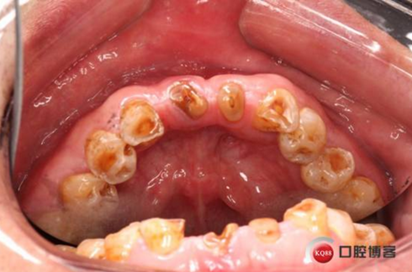

患者,男性,47歲,全身情況良好,無手術禁忌,口內(nèi)因下前牙缺損松動不美觀來院。初診檢查時發(fā)現(xiàn)患者前牙深覆合,下頜32、42缺失。31、41松動二度,切緣磨耗嚴重,可探及髓腔,無保留價值。X-RAY檢查顯示:下頜前牙區(qū)寬度狹窄,咬合空間不足,無法行常規(guī)種植修復.

下圖是術前資料